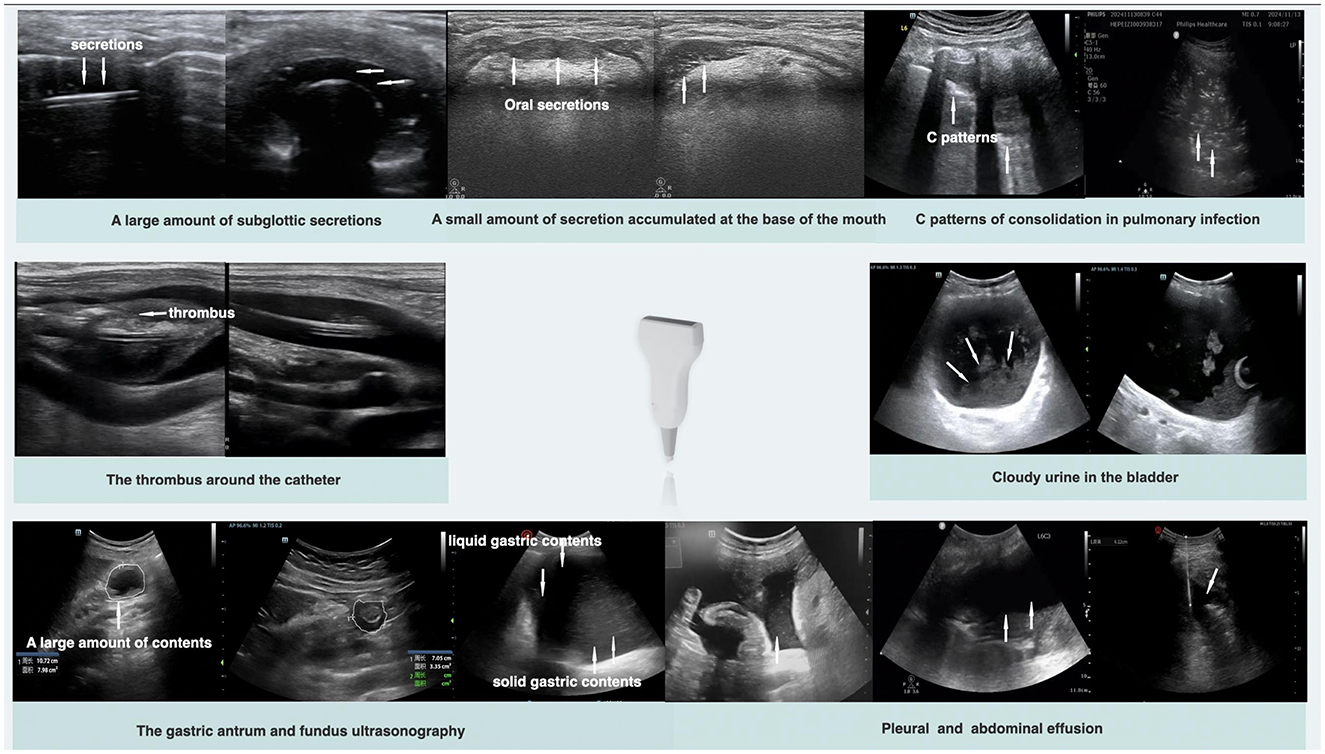

Given the aforementioned characteristics of ultrasound visualization technology, POCUS plays a significant role in infection control within healthcare settings. As shown in Figure 3, it enables direct observation of the accumulation of infectious secretions, evaluation of gastrointestinal and other organ functions, monitoring of pulmonary atelectasis, and assessment of the degree of barrier disruption. These capabilities make ultrasound an invaluable tool for implementing infection control measures, enabling real-time, dynamic adjustments to treatment plans and improving both the effectiveness of infection control and the precision of therapeutic interventions (33).

Figure 3

Ultrasound images showing various medical conditions. Top row: subglottic and oral secretions, secretions at mouth base, and pulmonary infection consolidation. Middle row: thrombus around a catheter and cloudy urine in the bladder. Bottom row: gastric antrum and fundus with contents and pleural and abdominal effusion. Each image is labeled with arrows indicating specific details.

Figure 3. Typical ultrasound images of the five lines.